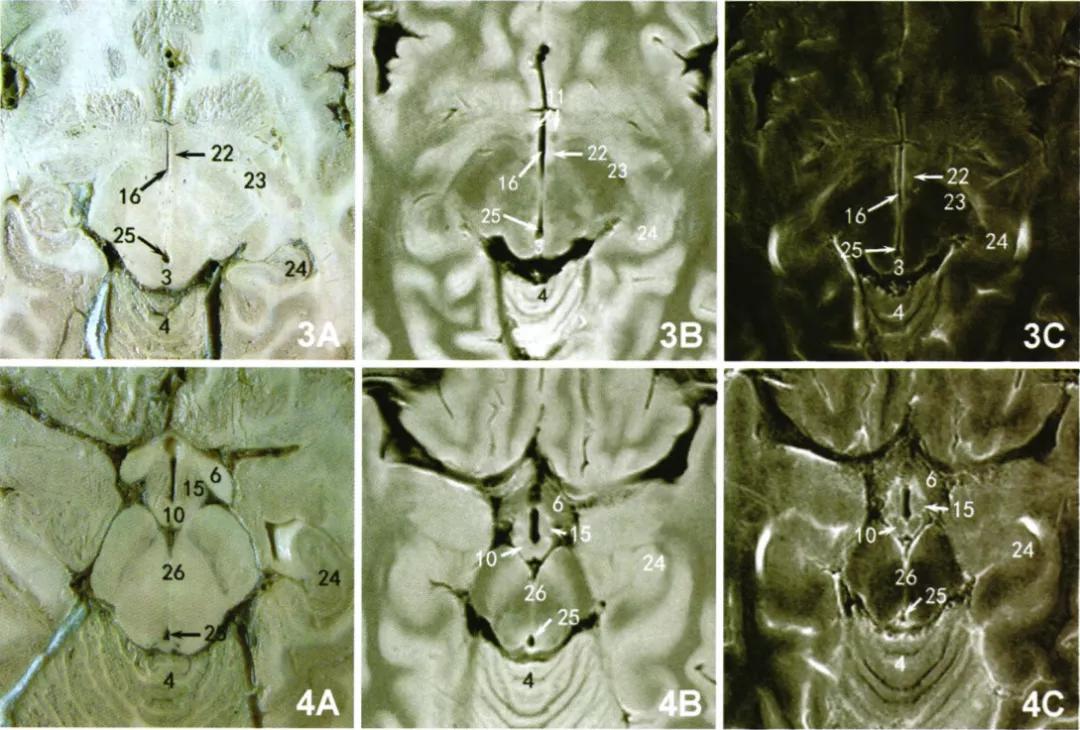

下丘脑室旁核在标本经大脑脚横断层面可见, 呈第三脑室前侧方脑实质内一条形灰质带(图3A)。对应同一标本同层面,T1WI图像中可见此核 团呈等信号,与周围白质结构分界清晰(图3B);T2WI可见第三脑室旁相同区域脑实质内发现一等信号区(图3C),其内侧为高信号的第三脑室内膜,前方可见低信号前连合,外侧面为低信号白质区。

乳头体核在标本经垂体正中矢状面旁及鞍上池横断面可清晰显示其结构形态(图1A,4A)。在MRI的T1WI图像中可清晰显示乳头体核呈卵圆形等信号区(图1B,4B),矢状面乳头体核边缘隐约可见包绕的略低白质样信号;T2WI图像中乳头体信号略显混杂,显示不清。此外,在矢状面MRI的T1WI中可清晰显示低信号的穹隆纤维投射进入乳头体核内。

视上核在标本经鞍上池横断面及经前连合冠状面可见核团位于视交叉上方,骑跨于视束上(图2A)。通过标本经前连合冠状切面观察,可见视束 上方下丘脑区一片状灰质,未见明显分界,在T1WI上可清晰显示此区呈等信号,与周围灰质结构未见明显分界。此区在T2WI图像上显示为与周围灰质相同的等信号区(图2B,2C,4B,4C)。